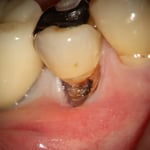

中央:歯と歯肉の境目に、圧排糸を挿入(麻酔をしてあります)します。※治療後、もちろん、圧排糸は除去します。

これは、歯を削ったあと、最終補綴物を作るための型採りの準備としての歯肉圧排です。

隣り合った歯と歯の間に入っている黒いものが圧排糸と呼ばれる専用の糸です。

さて、この症例の場合、歯と歯の間の距離はどれほどでしょうか?

金属の器具の先端の丸いボールの直径が約0.5mmですので、歯と歯の間は、約1mmです。

これは、左上の奥歯ですが、1mmしかない場所に、このように正確に糸が入ると思いますか?

型採りの時も顕微鏡を使っています。